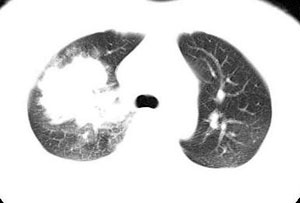

本病例特点如下:

1.青年女性,以胸痛20多天就诊,无呼吸道及感染临床症状体征,无原发肿瘤病史;

2.肺ct表现为两肺多发大小不等结节影,大结节位于肺尖部,小结节多位于肺外带胸膜下,大结节内可见支气管充气征,周围可见月晕征(指在结节状或肉芽肿样病灶周围呈环形磨玻璃影),右肺门及腔静脉后可见小淋巴结,右侧胸腔内少量液体。

两肺散在分布大小不等的肿块及结节影,边缘毛糙,有分叶、毛刺,病灶密度不均匀,可见支气管充气相与空泡征。病变大多位于胸膜下,可见胸膜凹陷及胸腔积液。气管腔静脉间可见小结节影。

病人临床仅为胸痛,暂不考虑感染性病变。

考虑多发结节型细支气管肺泡癌。